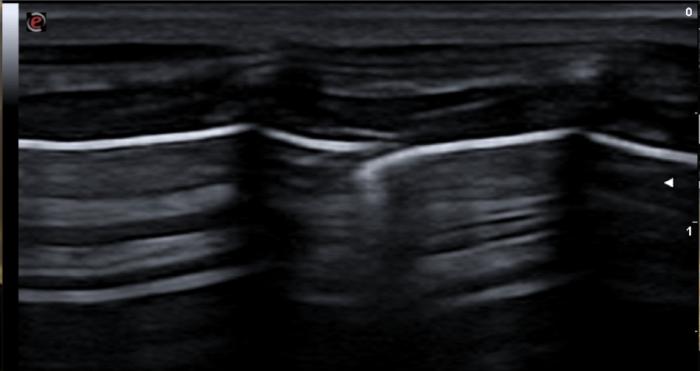

El signo de deslizamiento puede ser evaluado tanto en modo B como en modo M.

En caso de neumotórax severo con ocupación del receso costofrénico el signo de cortina se verá inalterado llamándose pseudo signo de cortina y siendo exactamente igual que el signo de cortina del paciente sano. En caso de neumotórax parcial, podemos ver el signo de cortina asincrónico, en el cual las vísceras abdominales se desplazan caudalmente en la inspiración y el signo de cortina lo hace cranealmente (al contrario que en el paciente sano) (Figura 8A-C).